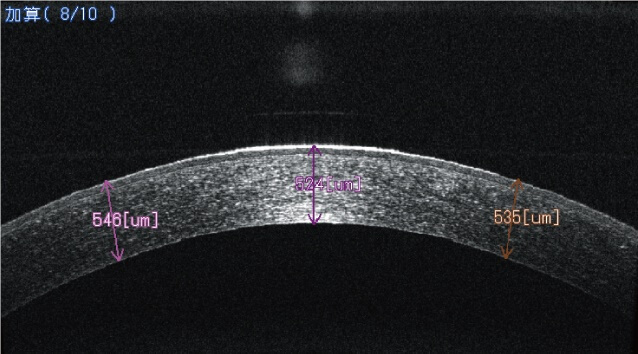

OCT角膜Radial撮影した正常眼の画像です

角膜 正常

中心角膜厚 正常値 517.5±29.8nm(ナノメートル)